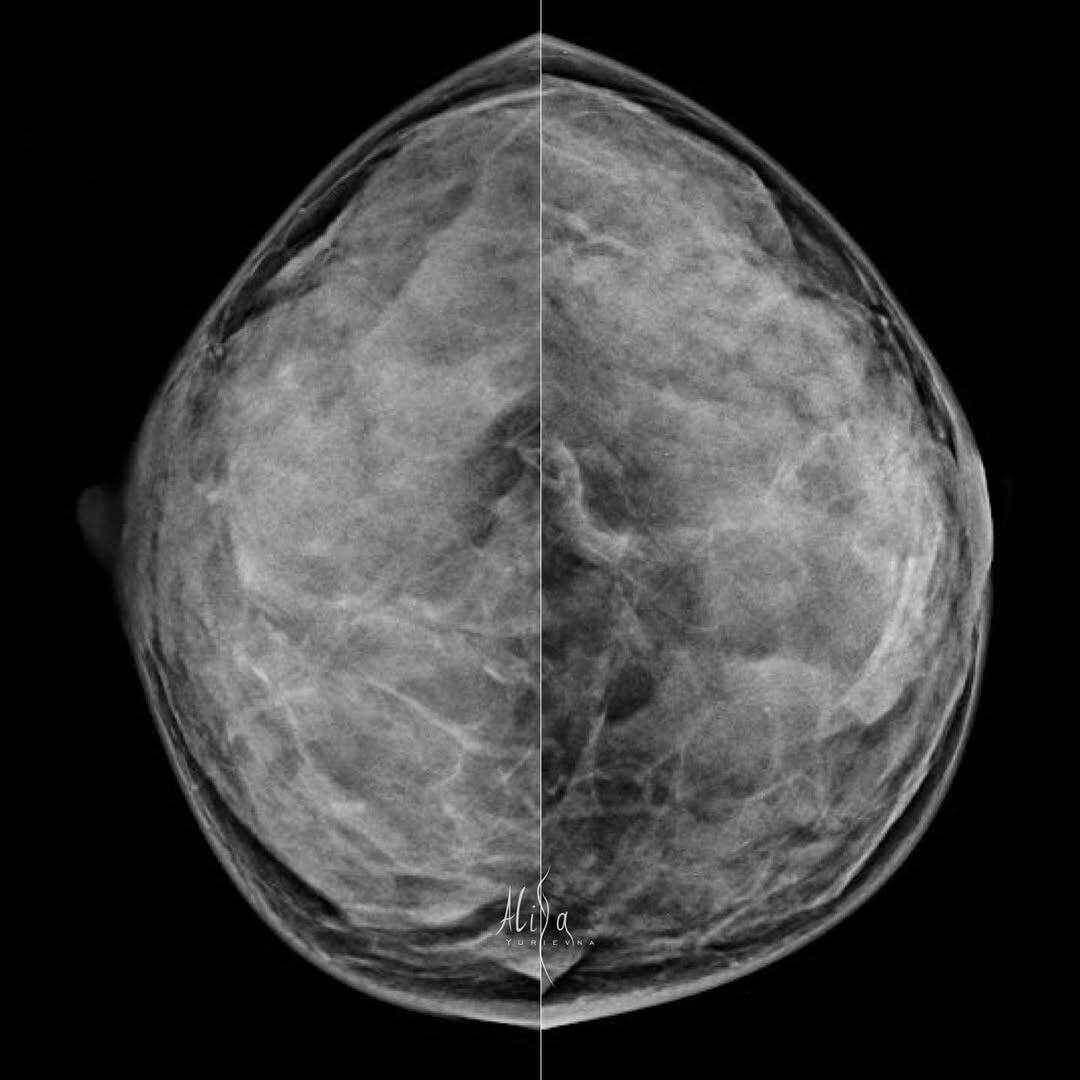

Кейс. Женщина 66 лет

Жалоб нет. Плотный рентгенологический фон. Всё как мы «любим». Выход единственный - освоить вторую модальность. УЗИ Молочных желёз. И плотная вуаль больше не будет преградой. ⠀ Инвазивная карцинома G1 молочной железы. Экспрессия рецепторов эстрогенов – 8 баллов, прогестеронов – 8 баллов, c-erbB2/HER2/neu – 1+. Маркер пролиферативной активности Ki67 имеют ~ 10% клеток. ⠀ #кейс

Жалоб нет. Плотный рентгенологический фон. Всё как мы «любим».

Выход единственный - освоить вторую модальность. УЗИ Молочных желёз. И плотная вуаль больше не будет преградой.

Инвазивная карцинома G1 молочной железы.

Экспрессия рецепторов эстрогенов – 8 баллов, прогестеронов – 8 баллов, c-erbB2/HER2/neu – 1+. Маркер пролиферативной активности Ki67 имеют ~ 10% клеток.